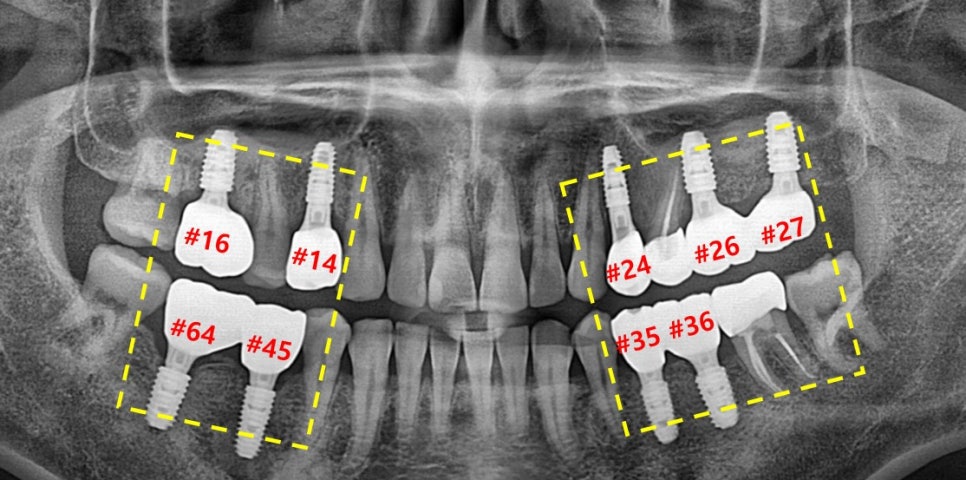

▲ 초진 파노라마 사진

표시된 곳들을 보시면 앞서 말씀드린 것과 같이 잔존 치근들만 남아있는 모습입니다.

노란 선으로 표시된 부분들은 보시면 잇몸뼈가 없어서 내려앉은 모습을 확인할 수 있습니다.

픽스처를 심을 잇몸뼈가 있어야 제대로 심고 잇몸뼈와 잘 결합이 될 수 있기에

#30번대 #40번대 뼈이식부터 먼저 도와드렸습니다.

▲치료 완료 후 파노라마 사진

이렇게 다른 구치부 치아들은 신경치료와 크라운 치료, 레진 치료

노란 박스로 표시된 치아들은 모두 임플란트 치료로 도와드렸습니다.